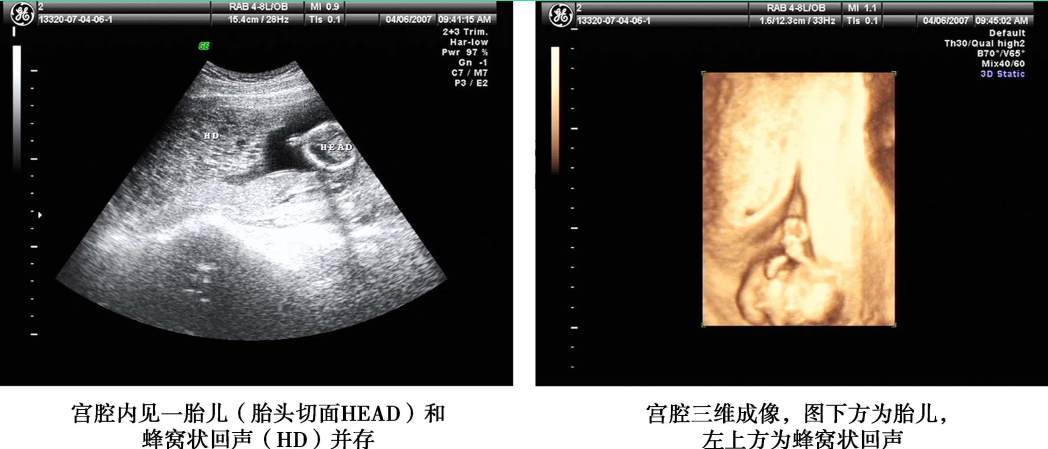

1.超声检查 是常用的辅助检查,最好采用经阴道彩色多普勒超声。完全性葡萄胎的典型超声图像为子官大于相应孕周,无妊娠囊或胎心搏动,宫腔内充满不均质密集状或短条状回声,呈“落雪状”,水泡较大时则呈“蜂窝状”。常可测到双側或一侧卵巢囊肿。彩色多普勒超声检查可见子宫动脉血流丰富,但子宫肌层内无血流或仅稀疏血流信号。部分性葡萄胎可在胎盘部位出现由局灶性水泡状胎块引起的超声图像改变,有时还可见胎儿或羊膜腔,胎儿通常畸形。早期葡萄胎妊娠的超声征象常不典型,容易误诊。

完全性葡萄胎超声影像(患者A)

完全性葡萄胎超声影像(患者B)

子宫增大,宫腔内充满蜂窝状不均质回声,大小7.5cm×6.3cm×5.3cm,内见众多大小不等暗区

部分性葡萄胎超声影像(患者A)

部分性葡萄胎超声影像(患者B)